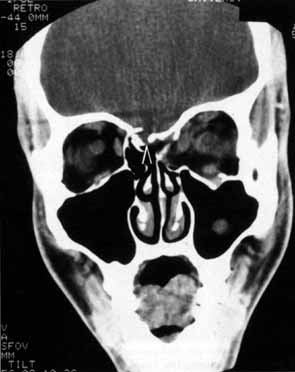

Anosmia caused by damage of cranial nerve I may be a helpful symptom of ethmoid or sphenoid sinus tumors invading the orbit (Fig. 20).44 Olfactory groove meningiomas and esthesioneuroblastomas may also present with anosmia prior to developing vision loss.45 Trauma that involves the orbit and is associated with anosmia should be considered a basilar skull fracture with potential for cerebrospinal fluid leak until proven otherwise (Fig. 21).

Fig. 20 A 13-year-old child presented with a 2-week history of sinusitis and anosmia. Her visual acuity decreased to to 20/400 1 day prior to admission. Computed tomography shows a large ethmoid tumor extending through the cribriform plate and optic canal. A rhabdomyosarcoma was diagnosed by biopsy.

Fig. 21 A 21-year-old man sustained a skull fracture from a motor vehicle accident 2 months prior to this examination. The patient describes anosmia since the accident. Computed tomography discloses a large medial wall orbital fracture extending through the cribriform plate (arrow). Orbital reconstruction was performed through a frontal craniotomy where dura was found incarcerated within the fracture. The orbital fracture was repaired by cranial bone grafting.